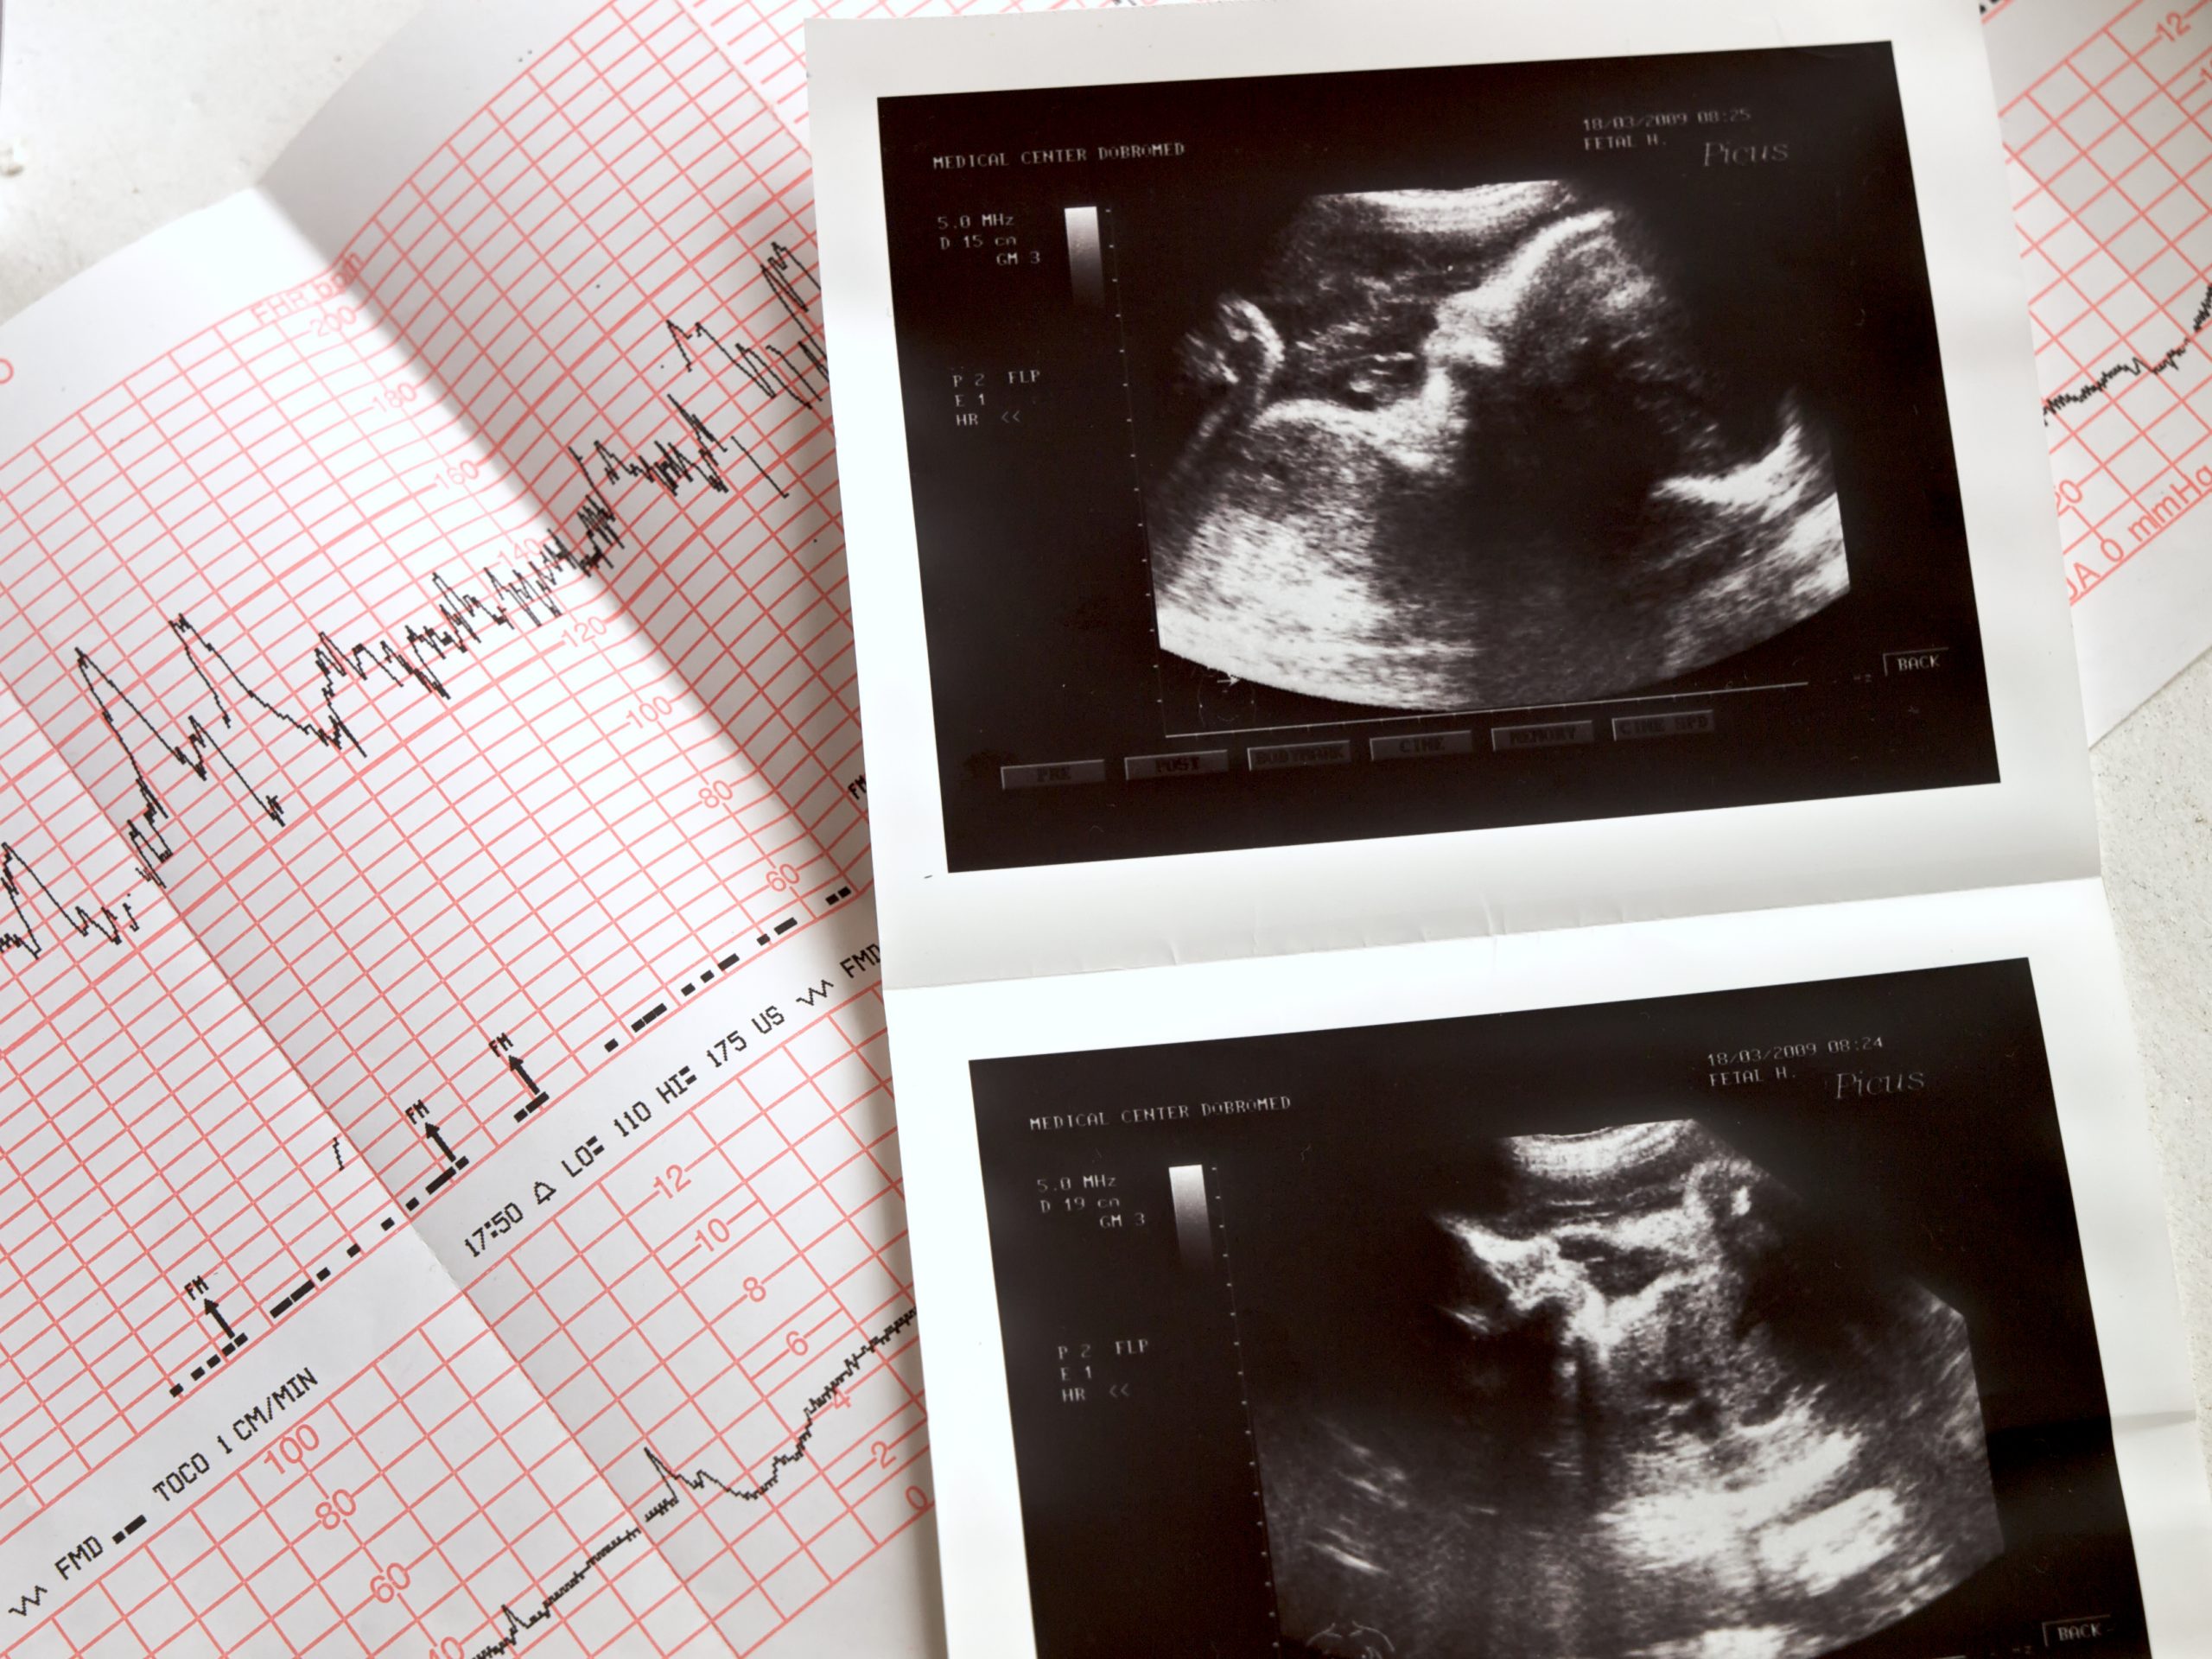

National Institutes of Health (Health and Human Services’ research branch) grantee Dr. Jörg C. Gerlach, an “experimental surgeon” at the taxpayer-funded University of Pittsburgh, has developed and published on a grotesque technique to harvest fresh, pristine livers from intact babies delivered alive in late-term abortions “at a gestational age of 18 to 22 weeks.” Gerlach’s liver-harvesting “protocol” is used for experimental stem cell transplants according to “current Good Manufacturing Practice,” or cGMP, guidelines developed by the U.S. Food and Drug Administration, another arm of HHS.

“The abortions associated with our protocol were performed by routine medical induction; the labor was induced by local prostaglandin administration,” wrote Gerlach and his University of Pittsburgh Medical Center team. “Because we obtained the tissue from intact abdomens and removed the livers surgically under cGMP conditions, the tissue could be obtained in a sterile manner.”

The FDA’s cGMP guidelines require sterile tissue transplantation products, which means the abortion must leave the fetus intact, with internal organs unexposed to external pathogens.

The step-by-step, clinical details of Gerlach’s experiments are surreal: “Fetuses were collected and transferred to the current good manufacturing practice (cGMP) facility for human cell processing.” How does an NIH-funded researcher “collect and transfer” a five-month old fetus? “The specimens were placed into sterile bags containing University of Wisconsin liver storage solution, and each specimen was transported on ice immediately after the abortion to minimize the transfer time until cell isolation.”

Immediacy was key: “The logistics of the transfer of the fetus to the cell isolation facility required no more than 1 hour, and our protocol excluded the use of cells that were isolated more than 6 hours prior to transplant.”

In vivo, of course, means “in the living.” To a medical certainty, a 5-month-old fetus aborted intact by labor induction is alive at the time of delivery. Feticides such as digoxin cannot be used in a harvesting case, and the whole point of the Gerlach protocol is to obtain fresh, live, clean liver cells for transplantation minimizing time without circulation.